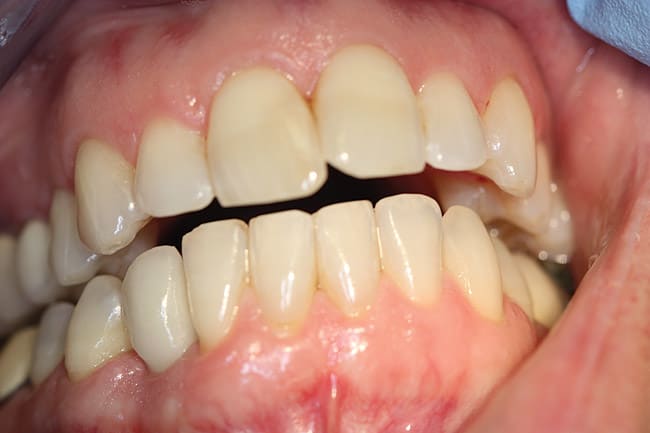

In another case showing the benefit of platform switching, a 40-year-old man presented with a missing lower right cuspid (Figure 7), which he reported was traumatically evulsed in a fistfight. He had limited finances and was unemployed for more than a year before he was able to afford to replace it. Since the two adjacent teeth were unrestored, he did not want to possibly damage them with crown abutments for a fixed bridge. He was offered a dental implant, restored with a single crown, and he accepted the treatment. Figure 8, a 2-year post-placement x-ray, shows no bone loss. A platform-switched abutment supports the crown on a 5.0-mm Hiossen implant with cervical microthreads at the top and placed with 60 newton centimeters torque. Figure 9 shows the final crown in place for 2 years, with optimal emergence profile and no tissue or bone loss. The microthreads have acted to stabilize the peri-implant marginal bone.